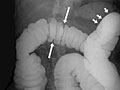

- In an air-contrast or double-contrast study, the colon is first filled with barium, and then the barium is drained out. This leaves only a thin layer of barium on the wall of the colon. The colon is then filled with air. This provides a detailed view of the inner surface of the colon. It makes it easier to see narrowed areas (strictures), diverticula, and swelling.

- Polyps or growths on the inner wall of the colon.

- Sacs in the colon wall (diverticulosis).

- Problems with defects and swelling (colitis) of the lining of the colon.

- A narrowed segment or a twisted loop of bowel, causing an obstruction.